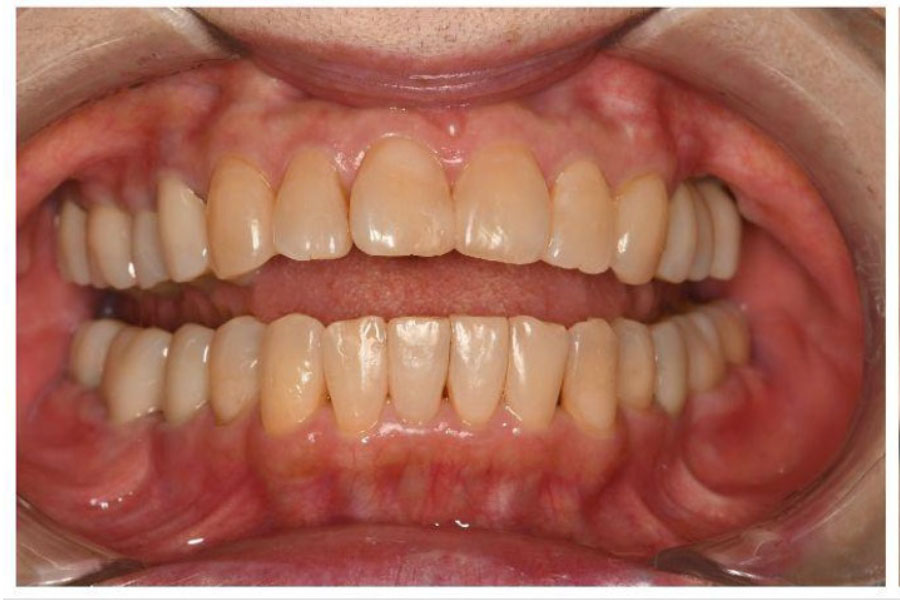

治療後